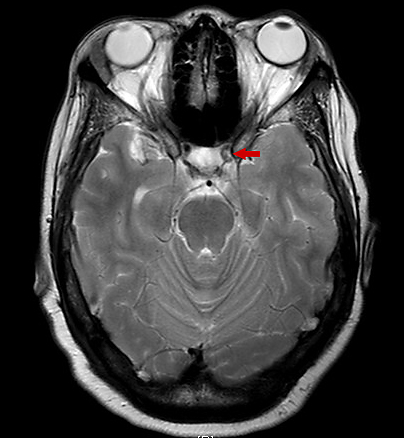

Findings of an MRI scan of the head were significant for multifocal bilateral subacute infarcts, predominantly scattered throughout the left cerebral hemisphere with superimposed multifocal remote infarcts, and vessel occlusion (Figures 1-3).

Figure 3